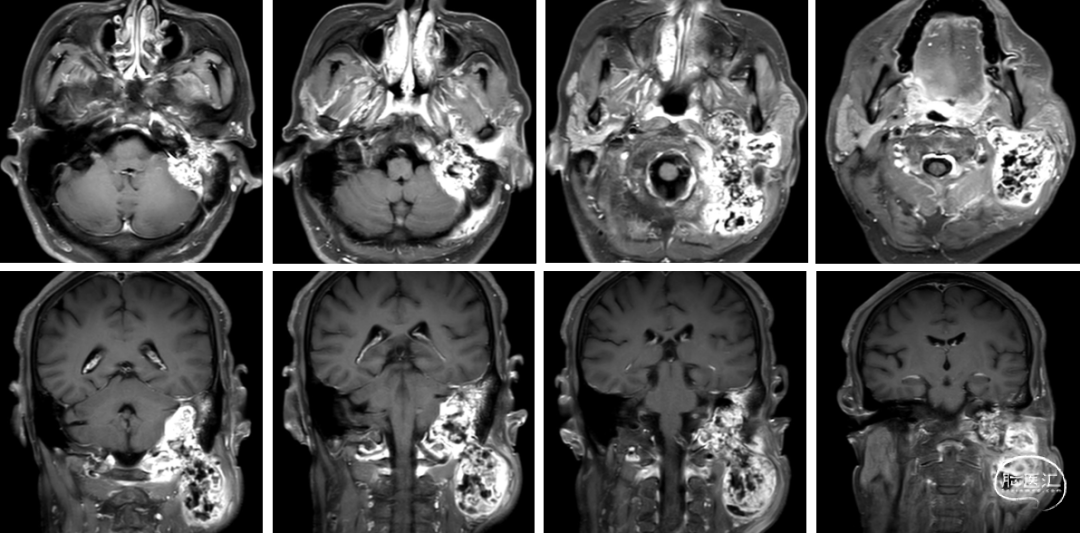

术前影像

术后影像

术后情况

患者术后恢复较好,面神经功能同术前,声音嘶哑、饮水呛咳症状同术前,无新发神经功能障碍。